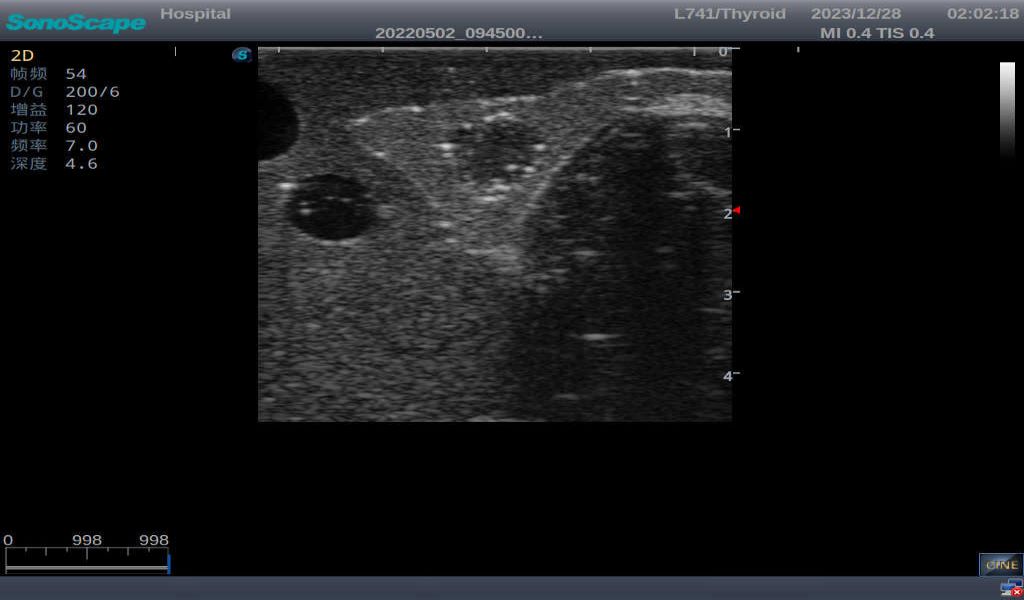

Normal thyroid with homogeneous parenchymal echo and well-defined capsule

Thyroid cyst, which fluid area, dark and echo-free area can be seen